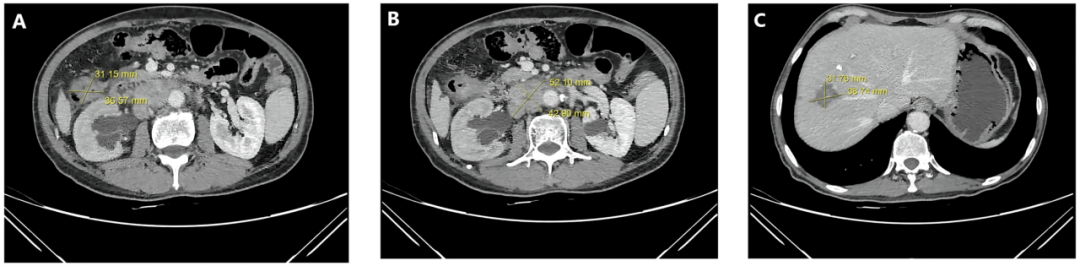

影像学检查显示,升结肠原发肿瘤大小为 4.9cm×4.4cm,腹膜后淋巴结转移灶达 8.4cm×4.7cm,肝右叶转移灶更是高达 10.3cm×8.7cm,病情已进入晚期,治疗难度极大。

A:结肠肿瘤CT图   B:淋巴肿瘤CT图   C:肝脏肿瘤CT图